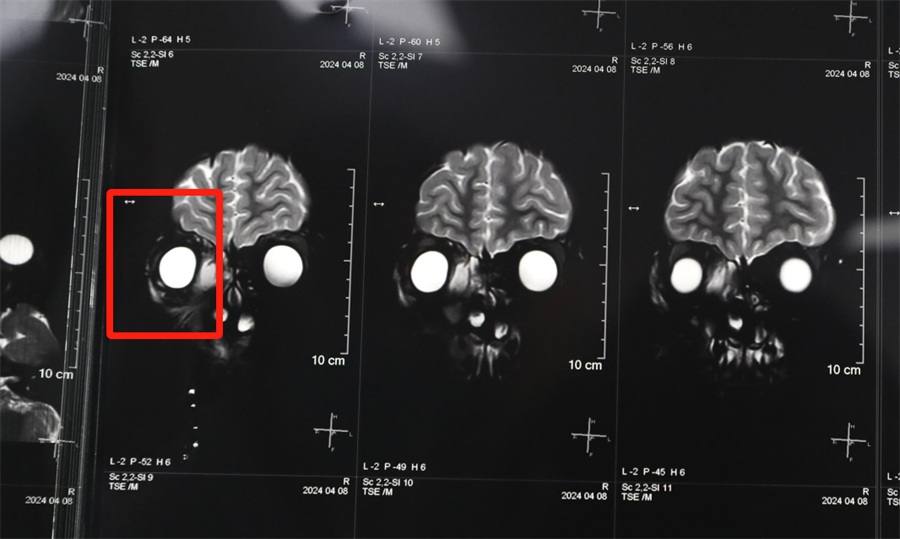

经眼科、耳鼻喉科联合会诊,医生发现孩子是因为患了急性鼻窦炎,导致右眼急性细菌感染,确诊为“右侧眶蜂窝织炎、眶内脓肿”。考虑到此病进展较快,可能导致视力下降甚至失明,耳鼻喉科立即将患儿收治入院。静脉输液、对症支持治疗、密切监测视力变化,一切有条不紊。入院第2天,孩子自觉右眼视力下降明显,眼科紧急会诊发现,其右眼视力从患病前的1.0下降到0.4。

北京儿童医院常驻专家、啪啪网 副院长杨小健决定立即手术治疗引流眶内脓液,并组织多学科联合会诊。考虑到患儿年龄较小,杨小健副院长决定采取内镜经鼻腔手术引流脓液,这种手术方式创伤小、恢复快、效果确切,而且避免了外切口瘢痕,不需要反复进行局部消毒换药。但是孩子鼻腔解剖结构本身就狭窄,而且处于急性感染期,术中出血风险较大,手术难度较高,对麻醉技术也有着很高的要求。

孩子左侧鼻腔3年来没有通气,鼻腔的发育受到了严重影响,甚至部分结构出现了一定程度的萎缩,并患有严重的鼻窦炎。杨小健副院长认真分析了孩子的病情,认为应该尽快手术治疗。